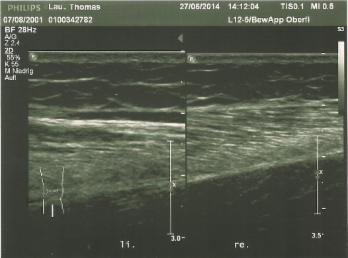

Zur Verdeutlichung:

li. ein normaler Muskel re. geschädigter Muskel meines Sohnes

mit normaler Struktur wattebauschartige Struktur